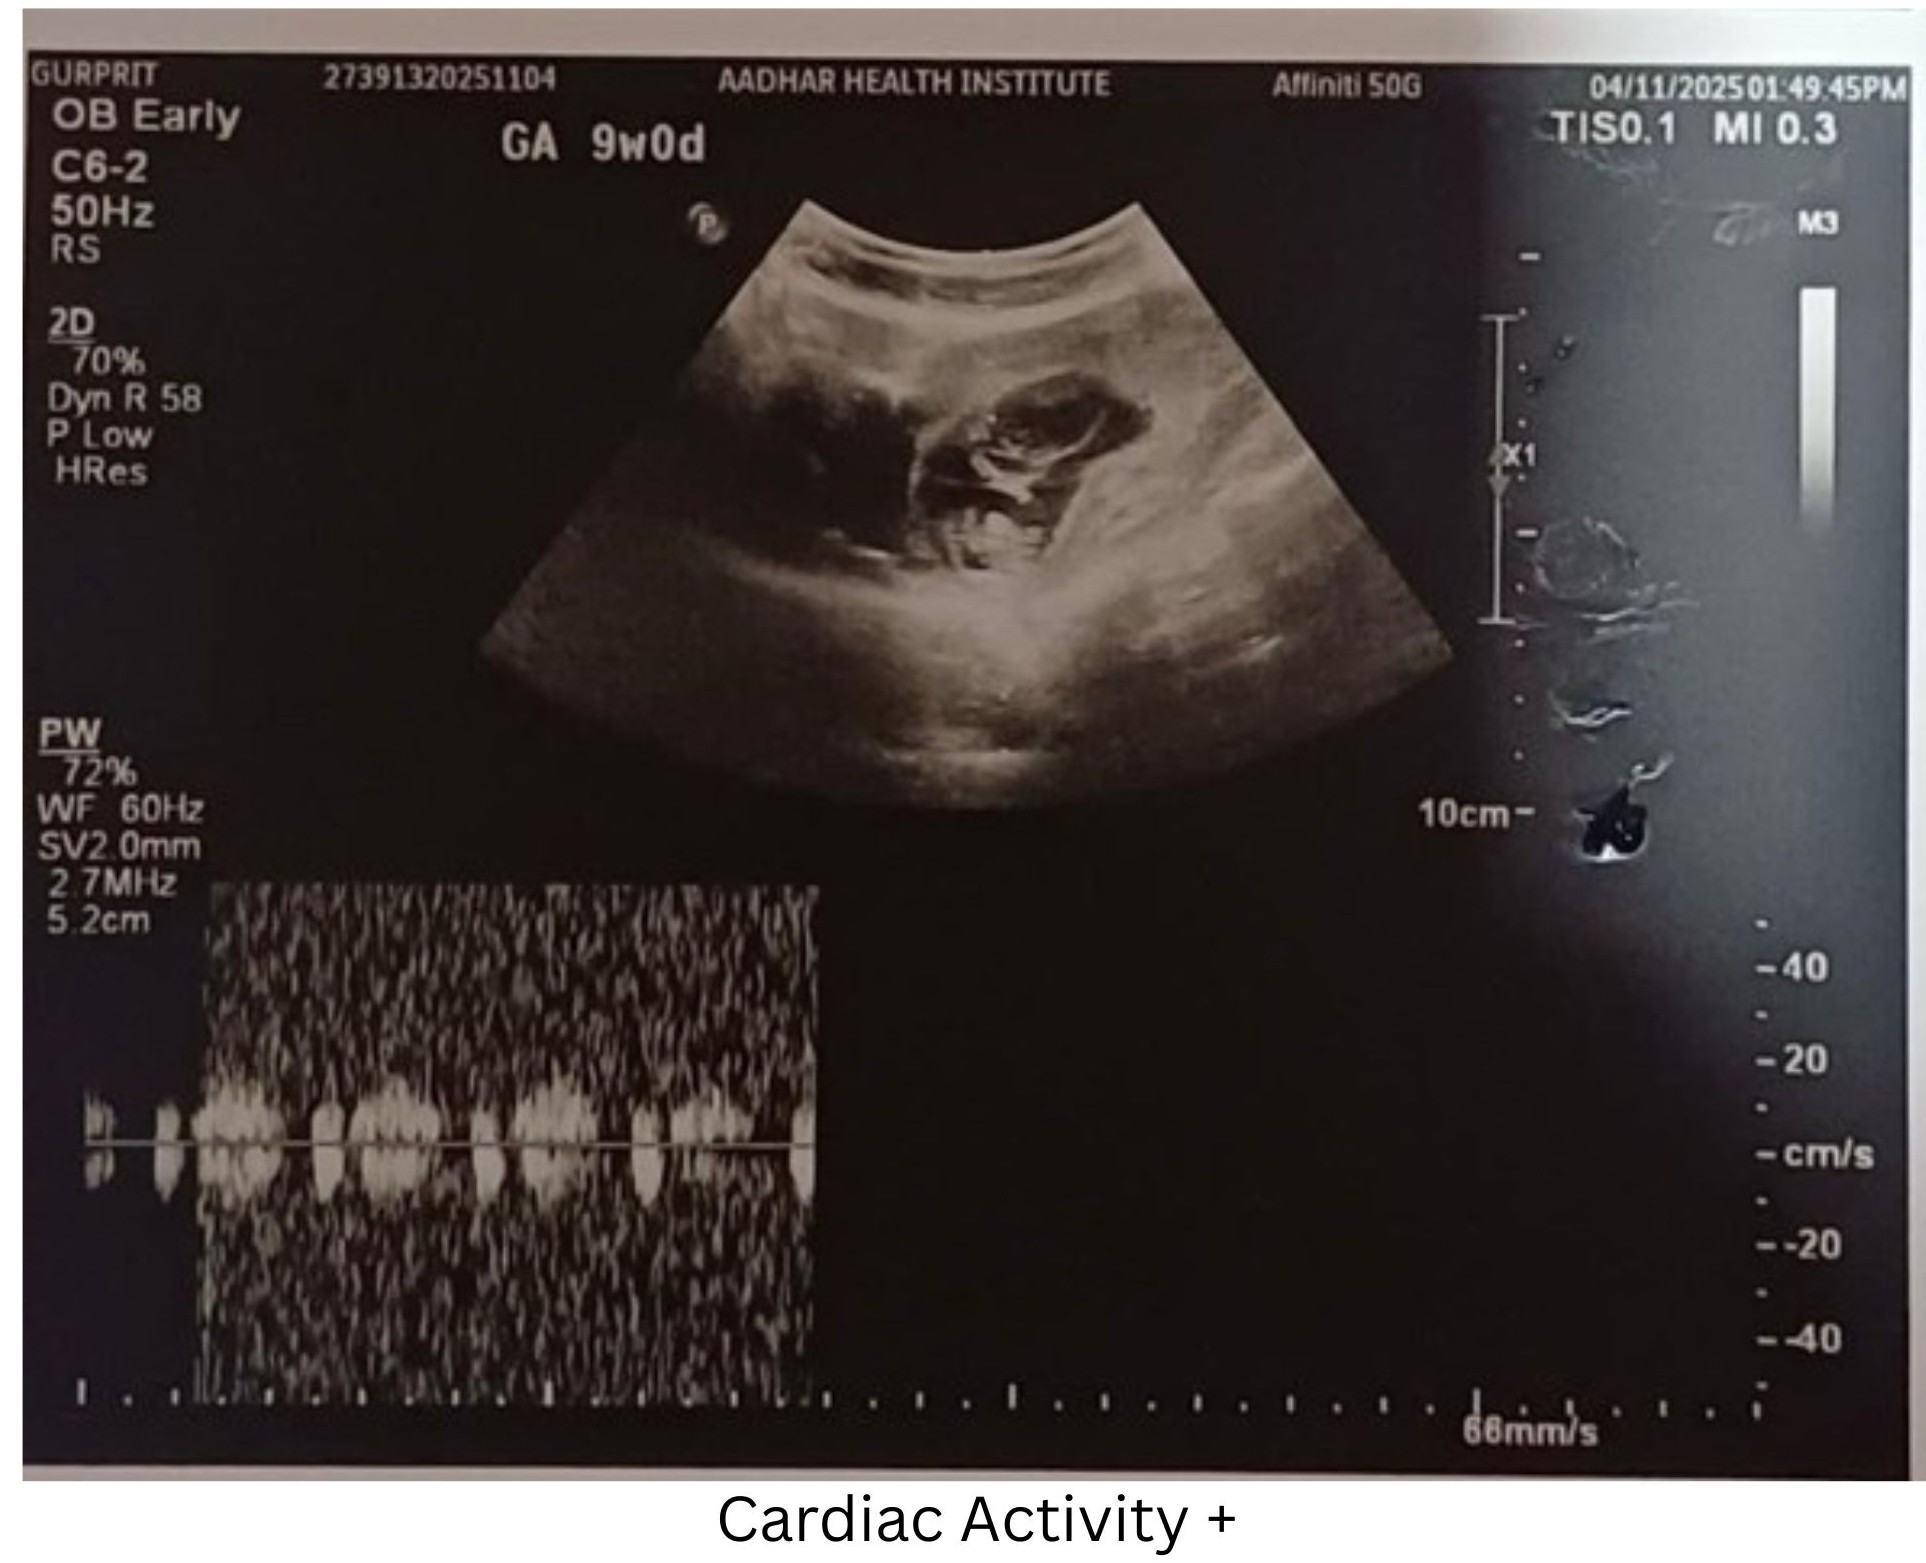

A 28-year-old female presented for a routine early pregnancy ultrasound at 9 weeks of gestation.

Cardiac activity present

A well-marginated heteroechoic lesion projecting into the gestational sac from the chorionic wall

No internal vascularity on Color Doppler